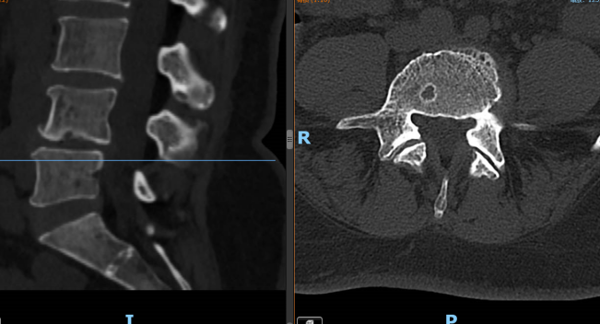

▲③术前CT片

“医生,我这半年来腰痛的厉害,右腿现在又痛又麻,走路都困难,有什么办法处理吗?”在骨科诊室,患者谭阿姨(化名)苦恼地说道。老虎机app 骨科脊柱外科专业专家欧裕福副主任医师详细询问谭阿姨病史,并为她安排了细致的检查,最终诊断为腰椎管狭窄症+腰椎滑脱症。

结合谭阿姨下腰部明显压痛、右下肢疼痛及活动障碍等症状,骨科脊柱外科团队经过多次术前讨论,并联合麻醉手术中心团队,为谭阿姨制定了个性化的诊疗方案,决定运用经皮内镜下腰椎减压融合技术为患者进行治疗。

术后第一天,医生为谭阿姨伤口换药并为他进行了腰椎X线及CT复查,显示手术后内固定植入物固定良好,椎间融合器放置在位,下肢麻木及疼痛症状明显好转。经过一系列的康复锻炼,谭阿姨术后第二天下床行走,术后5天办理出院。